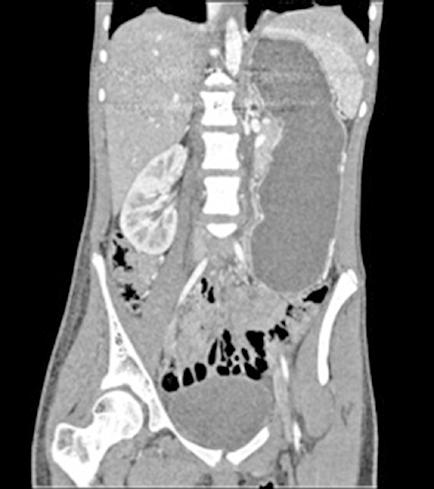

Tres meses después se realiza un nuevo TC de control, que muestra la lesión en el mismo lugar, actualmente de 7,4x5,9 cm de diámetros (previo de 9,8x7,5 cm). En la actualidad se ha alejado de las VSH, pero contacta y desplaza la vena porta derecha y la arteria hepática. Además se visualiza una leve dilatación de la vía biliar intrahepática izquierda, de nueva aparición. Se presenta en comité una vez más y se decide colocar un drenaje biliar interno-externo, dado la dilatación de vía biliar que presenta el paciente. Además se realiza una embolización portal derecha, para así aumentar el remanente del hígado izquierdo que era del 29%. Se realiza una nueva volumetría hepática tras la embolización portal y se comprueba que el futuro remanente hepático había aumentado al 42%.

Resumiendo: Teníamos una masa hepática inicialmente irresecable que se ha tratado con dos embolizaciones arteriales, consiguiendo una disminución del tamaño y una mayor separación de las venas suprahepáticas. Sin embargo, se ha acercado a la bifurcación portal y comprime la vía biliar (dilata la vía intrahepática izquierda asociando una elevación de bilirrubina). Se ha colocado un drenaje biliar interno-externo. Se ha embolizado la porta derecha, consiguiendo pasar de un volumen de remante hepático del 29% al 42%, siendo ahora posible su resección. El acceso a las VSH sigue siendo complejo y arriesgado, pero menos que al inicio (Figura 4).

Figura 4.

TC realizado tras las dos embolizaciones arteriales. Vemos cómo la lesión ha disminuido considerablemente de tamaño y ahora está más alejada de las VSH y de la cava. Esto permite la ligadura de las VSH en su confluencia con la cava. Inicialmente no habría sido posible por su cercanía y tamaño.